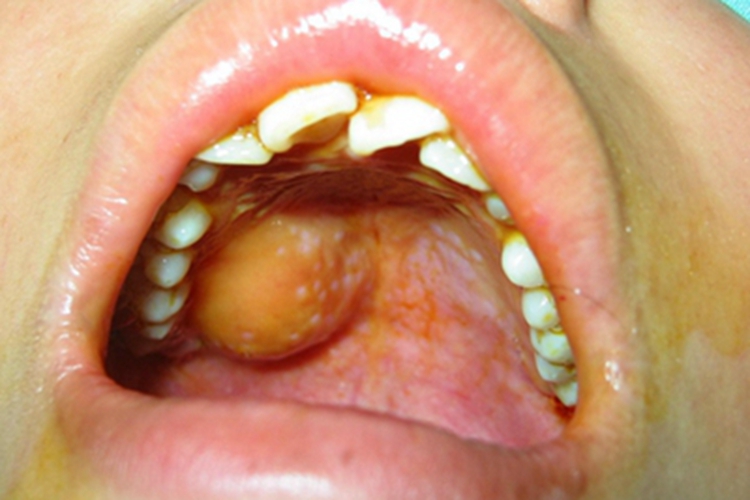

成人型纤维肉瘤生长在患者口腔时,表现为体积较大的肿块,呈半球形,颜色呈淡黄色,和周围皮肤分界明显,患者有轻微异物感,有时有疼痛感。